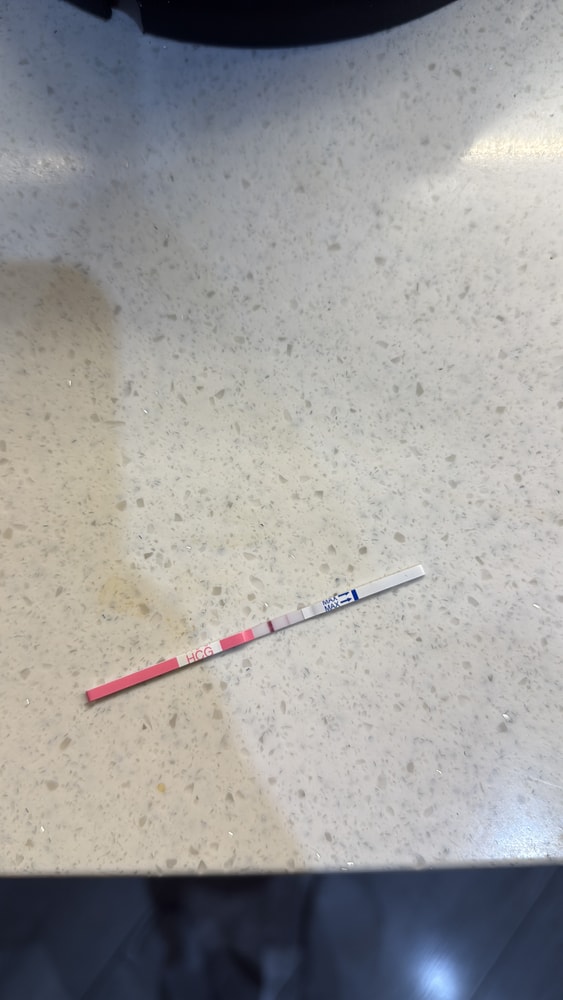

12ДПО положительный тест и ощущения

В общем, с 10дпо тест полосатится. Принимаю утрожестан. Сегодня уже 12 дпо, из ощущений почти каждые 2-3часа резкий прилив голода, желудок сосет прям) грудь болит) как думаете не рано ли началось то что желудок сосет сильно каждые 2 часа ? ))